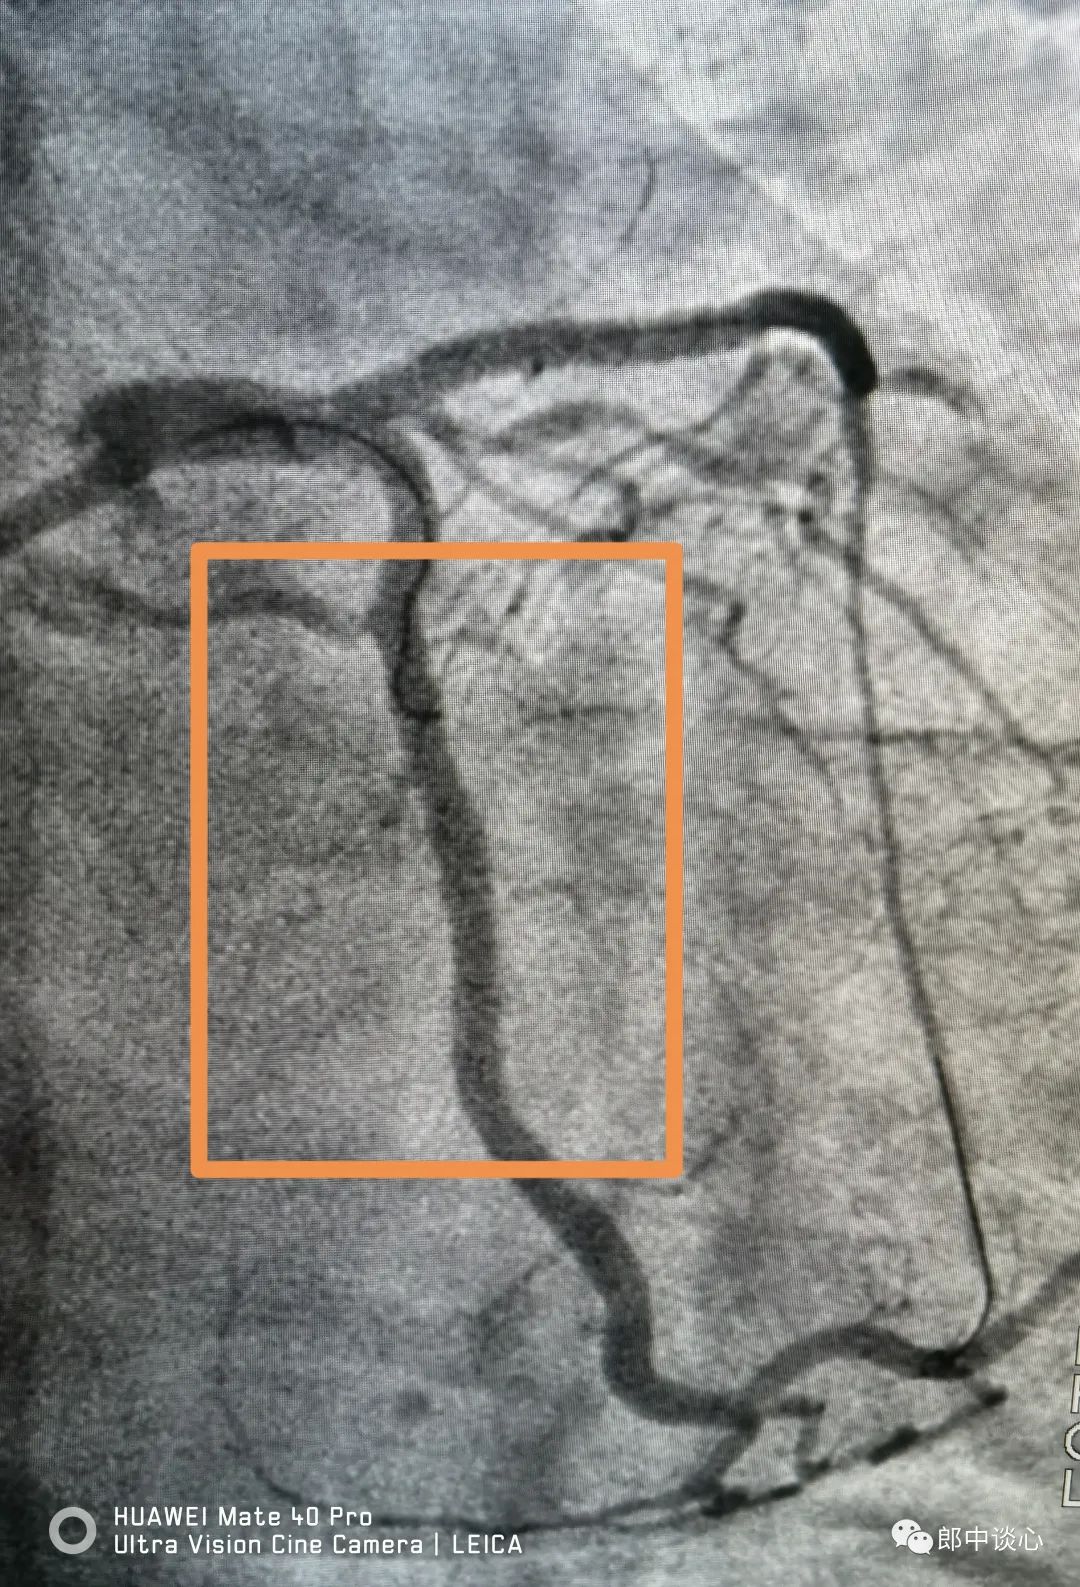

是不是感觉这个植入了近10年的支架很不错啊。今天再造影,成了下面这个你无法想象的样子。其实,这真的已经不是原来支架的错了!

问医问病问自己。病人自己交代,疫情期间他汀没了就没吃,连阿司匹林都在减半服用……。我也没啥话好说了!好在他也及时来医院了。